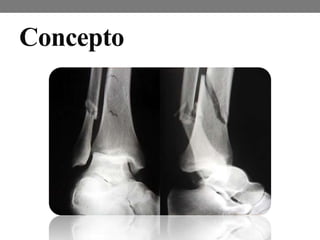

Concepto